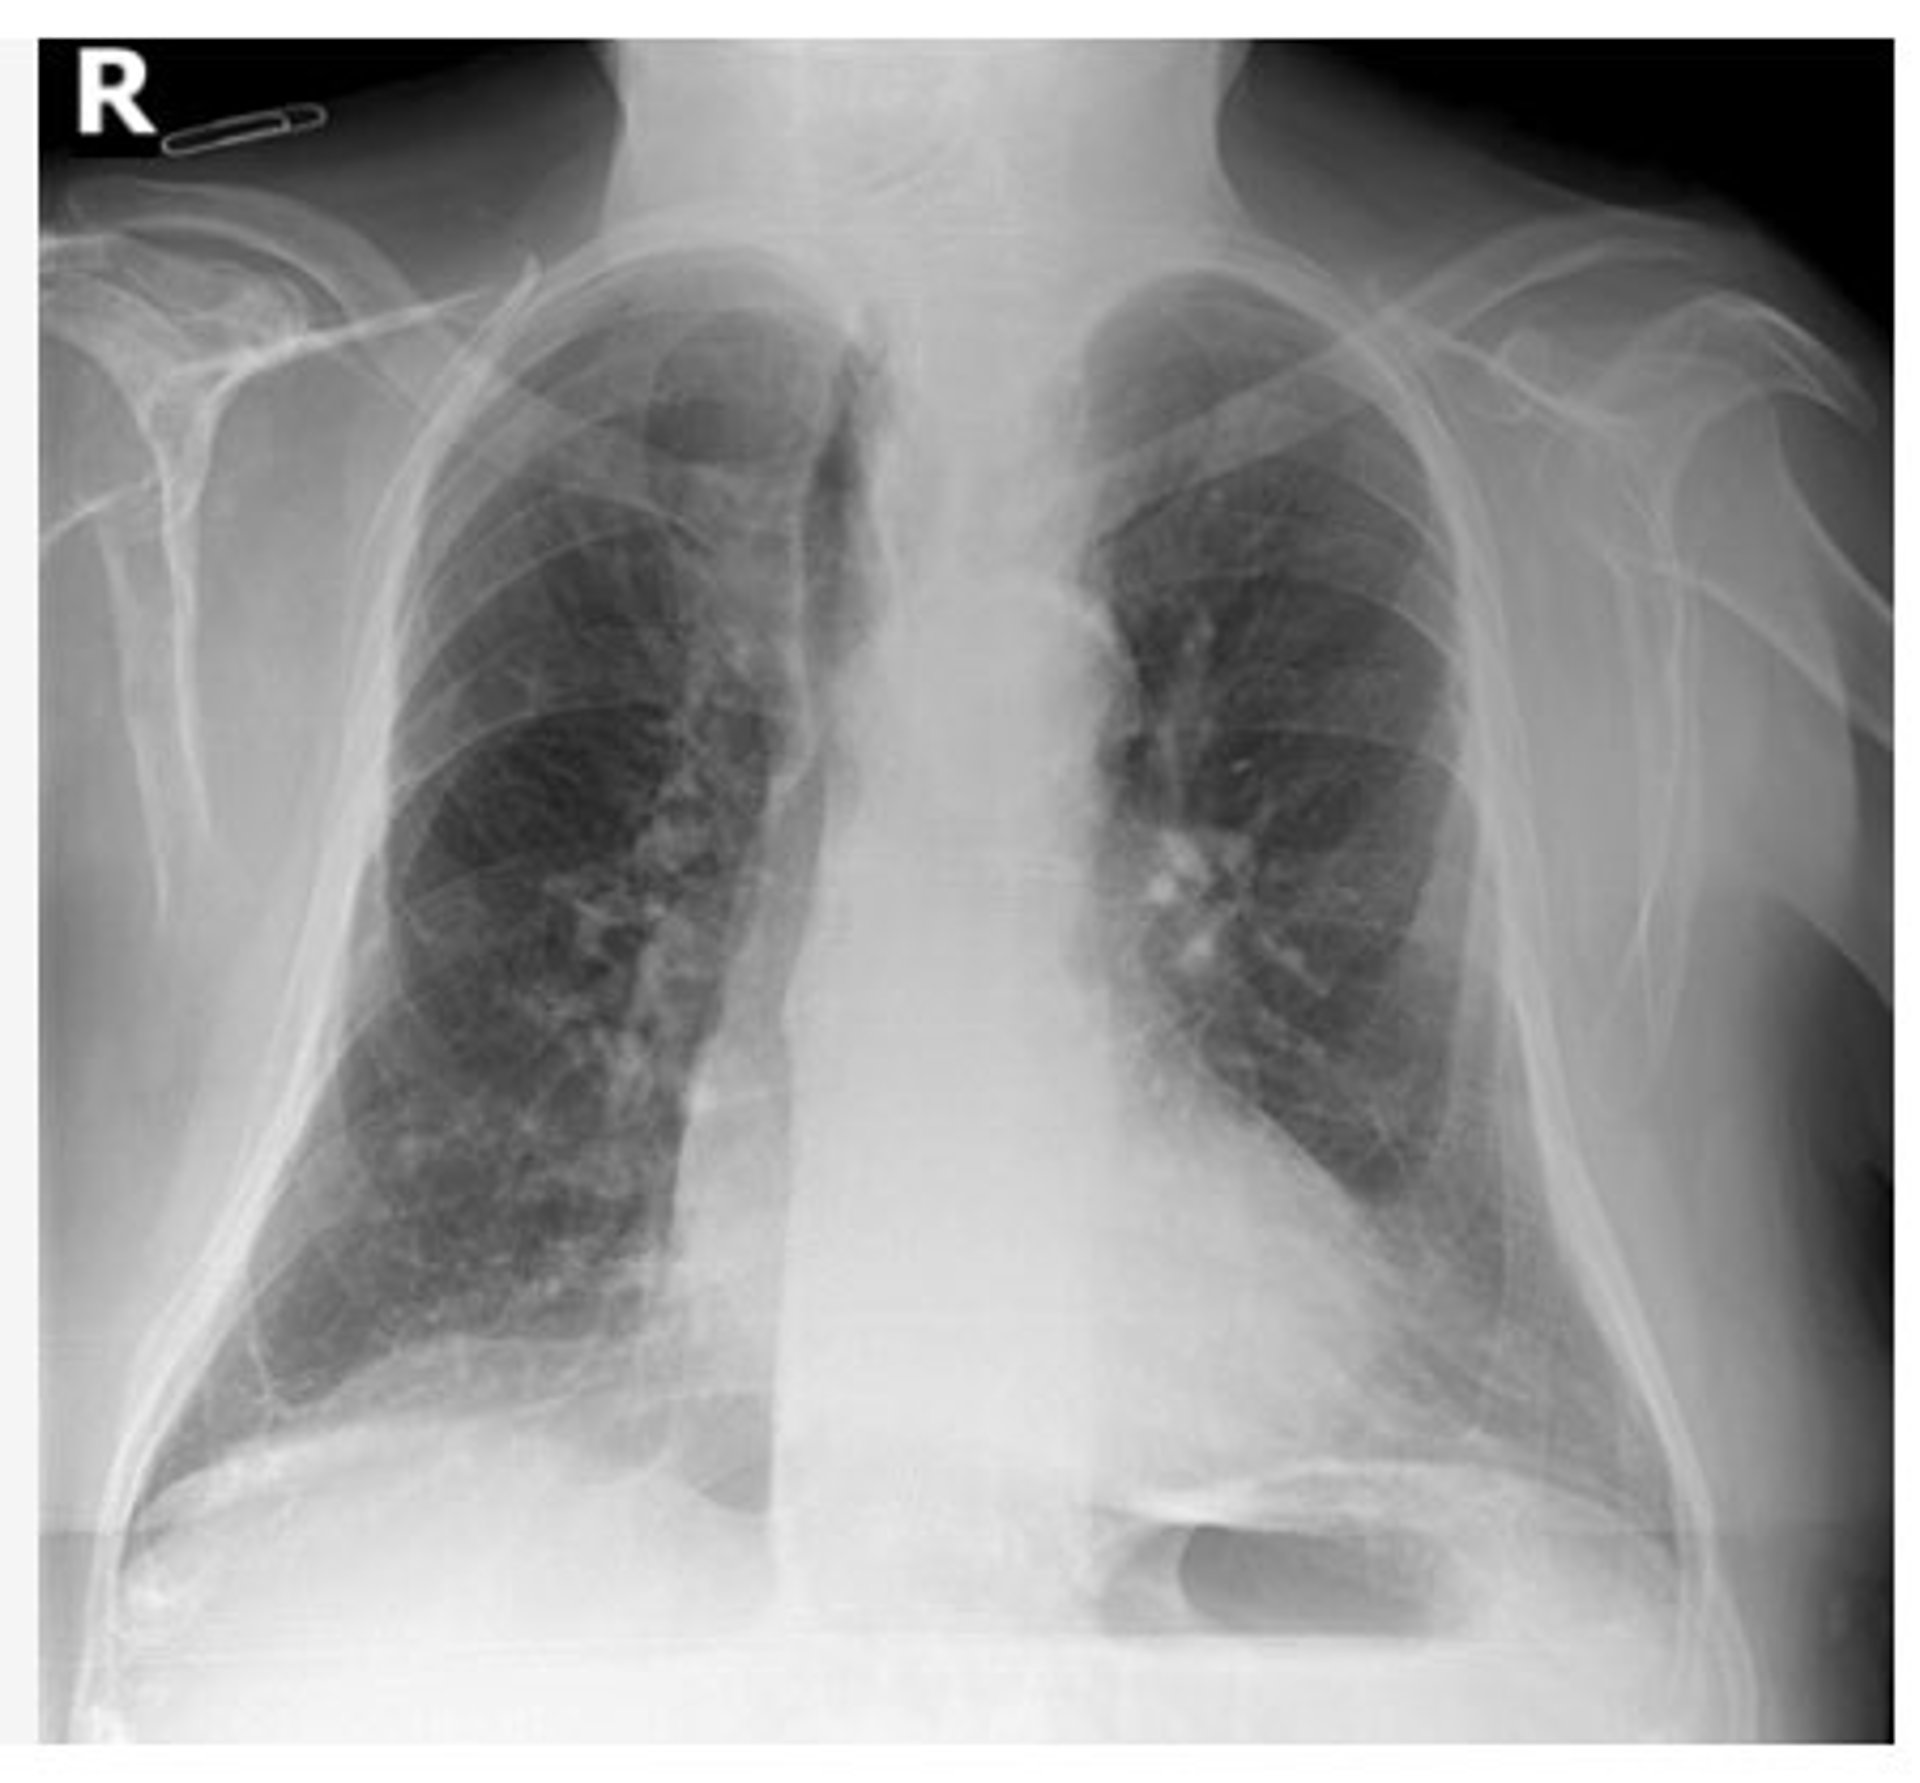

Archivo - Radiografía de tórax

Archivo - Radiografía de tórax - GVA - Archivo